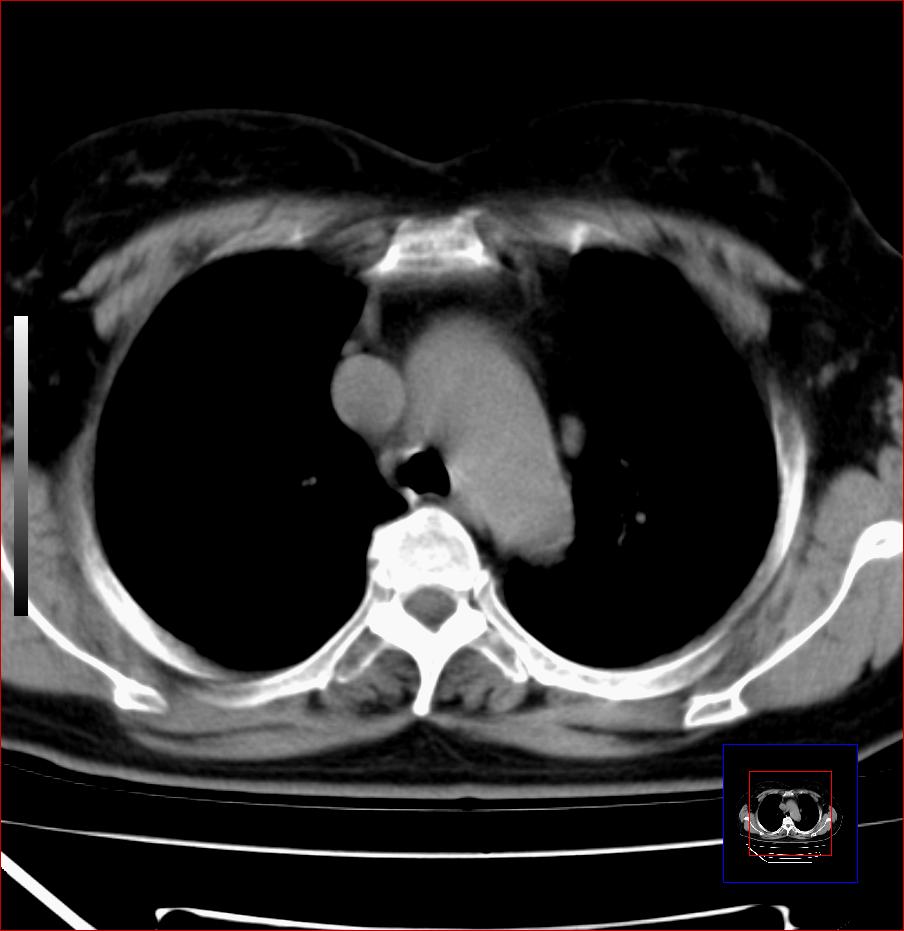

标题: CT25445:上段食管正常吗?

女,56岁,胸部体检,无不适。感觉食管壁略厚,最后约6mm.谢谢大家讨论,主要是自己亲人,疑神疑鬼的。主动脉弓旁淋巴结还有点肿大。

食管上三分之一段为横纹肌含气少或无 管壁可以厚些